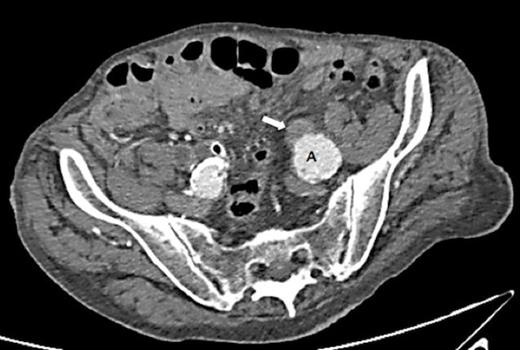

A 90 year old gentleman was admitted with haematuria and acute painful urinary clot retention. Prior to admission, he reported a 6 month history of intermittent visible haematuria. His past medical history included Duke’s A rectal carcinoma, hypertension and ischaemic heart disease. His haemoglobin count was 8.7g/dL and his renal function was normal. He was catheterised using a 3-way catheter with supplementary bladder washouts and received a 2 unit blood transfusion. Abdominal ultrasound revealed moderate left hydronephrosis. A CT urogram detected a 48mm infra-renal aortic aneurysm with bilateral iliac artery aneurysms – 33mm left, 31mm right. This scan also identified moderate to severe hydronephrosis on the left side with hydroureter extending down to the level of the iliac aneurysm (Fig. 1 & 2). There was no obvious fistula between the left ureter and the iliac aneurysm.

CT scan demonstrating hydronephrosis and hydroureter on the left side